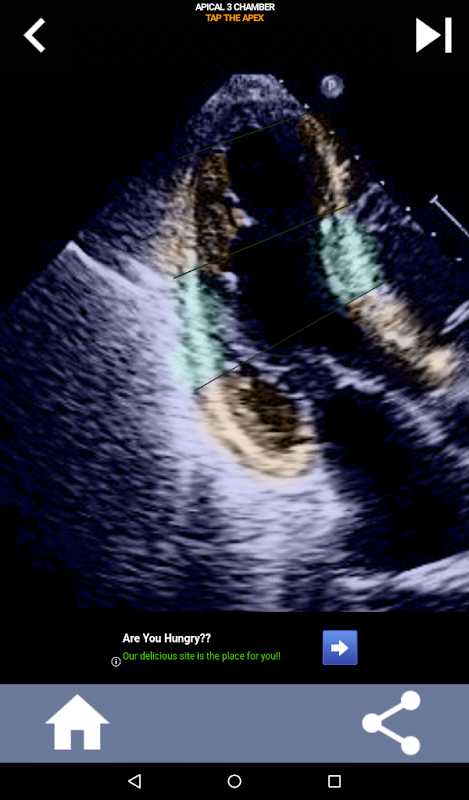

Diese App enthält alle Echoansichten, die das AHA-segmentierte Myokard anzeigen, und fragt Sie, ob Sie das richtige Segment antippen möchten. Ich persönlich finde, dass sich wiederholendes Quiz am besten für mich eignet, wenn ich das Thema schnell lernen / auswendig lernen muss. Wenn Sie ein Ultraschall-Student sind, der Echo / TTE studiert, ist dies meiner Meinung nach eine hervorragende Ergänzung zu Ihrem Studium.